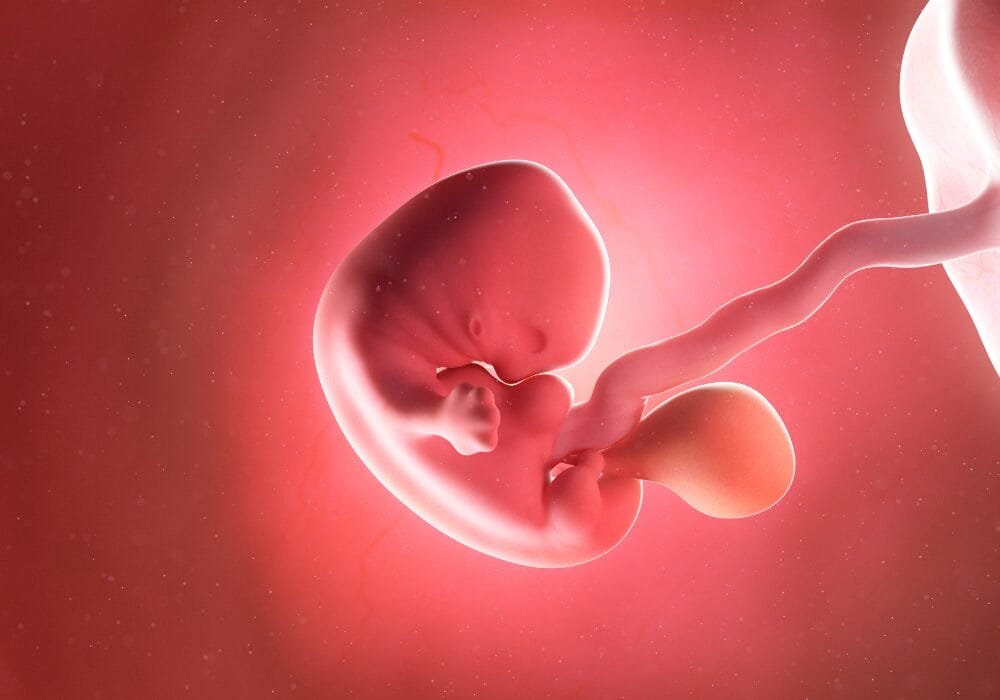

الأسبوع الخامس من الحمل يطلق على هذه الفترة بالفترة الجنينية حيث تبدأ أعضاء جسم الجنين بالتكون مثل القلب والجهاز العصبي والرئتين، ويمكن الشعور بنبض الجنين بداية من الأسبوع الخامس، ويمكن توضيح تطور نموه من خلال تكون الأديم الظاهر الخارجي الذي سيشكل الجهاز العصبي والأعضاء الخارجية مثل العينين والاذنين والعديد من الأنسجة، كما يتكون الأديم الداخلي وهو ما سيشكل الأعضاء الداخلية للإنسان، ويتكون الأديم الأوسط.

حجم طفلك في هذا الأسبوع

حجم طفلك في هذا الأسبوع يشبه إلي حد كبير حبة فلفل الأسود متناهي الصغر، ويتكون في داخله الكيس الصفار: وهو عبارة عن كيس مبطن بالغشاء يقوم بدوره بالتغذية خلال المراحل المبكرة الأولي لنمو الجنين داخل رحم الأم

يبلغ طوله : 0.05 in

يبلغ وزنه : 0.04 oz